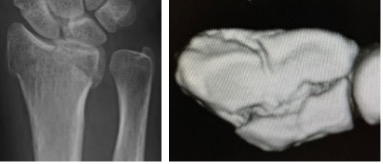

人工関節置換術

関節リウマチや変形性関節症の患者さんで、関節が破壊され機能が失われた症例に対し各関節(指、肘、肩)の人工関節置換術を行ない、関節機能の再建を行っています。

術前

右中指が屈曲変形し骨が癒合しています

術後

人工関節に置換し指が伸びました